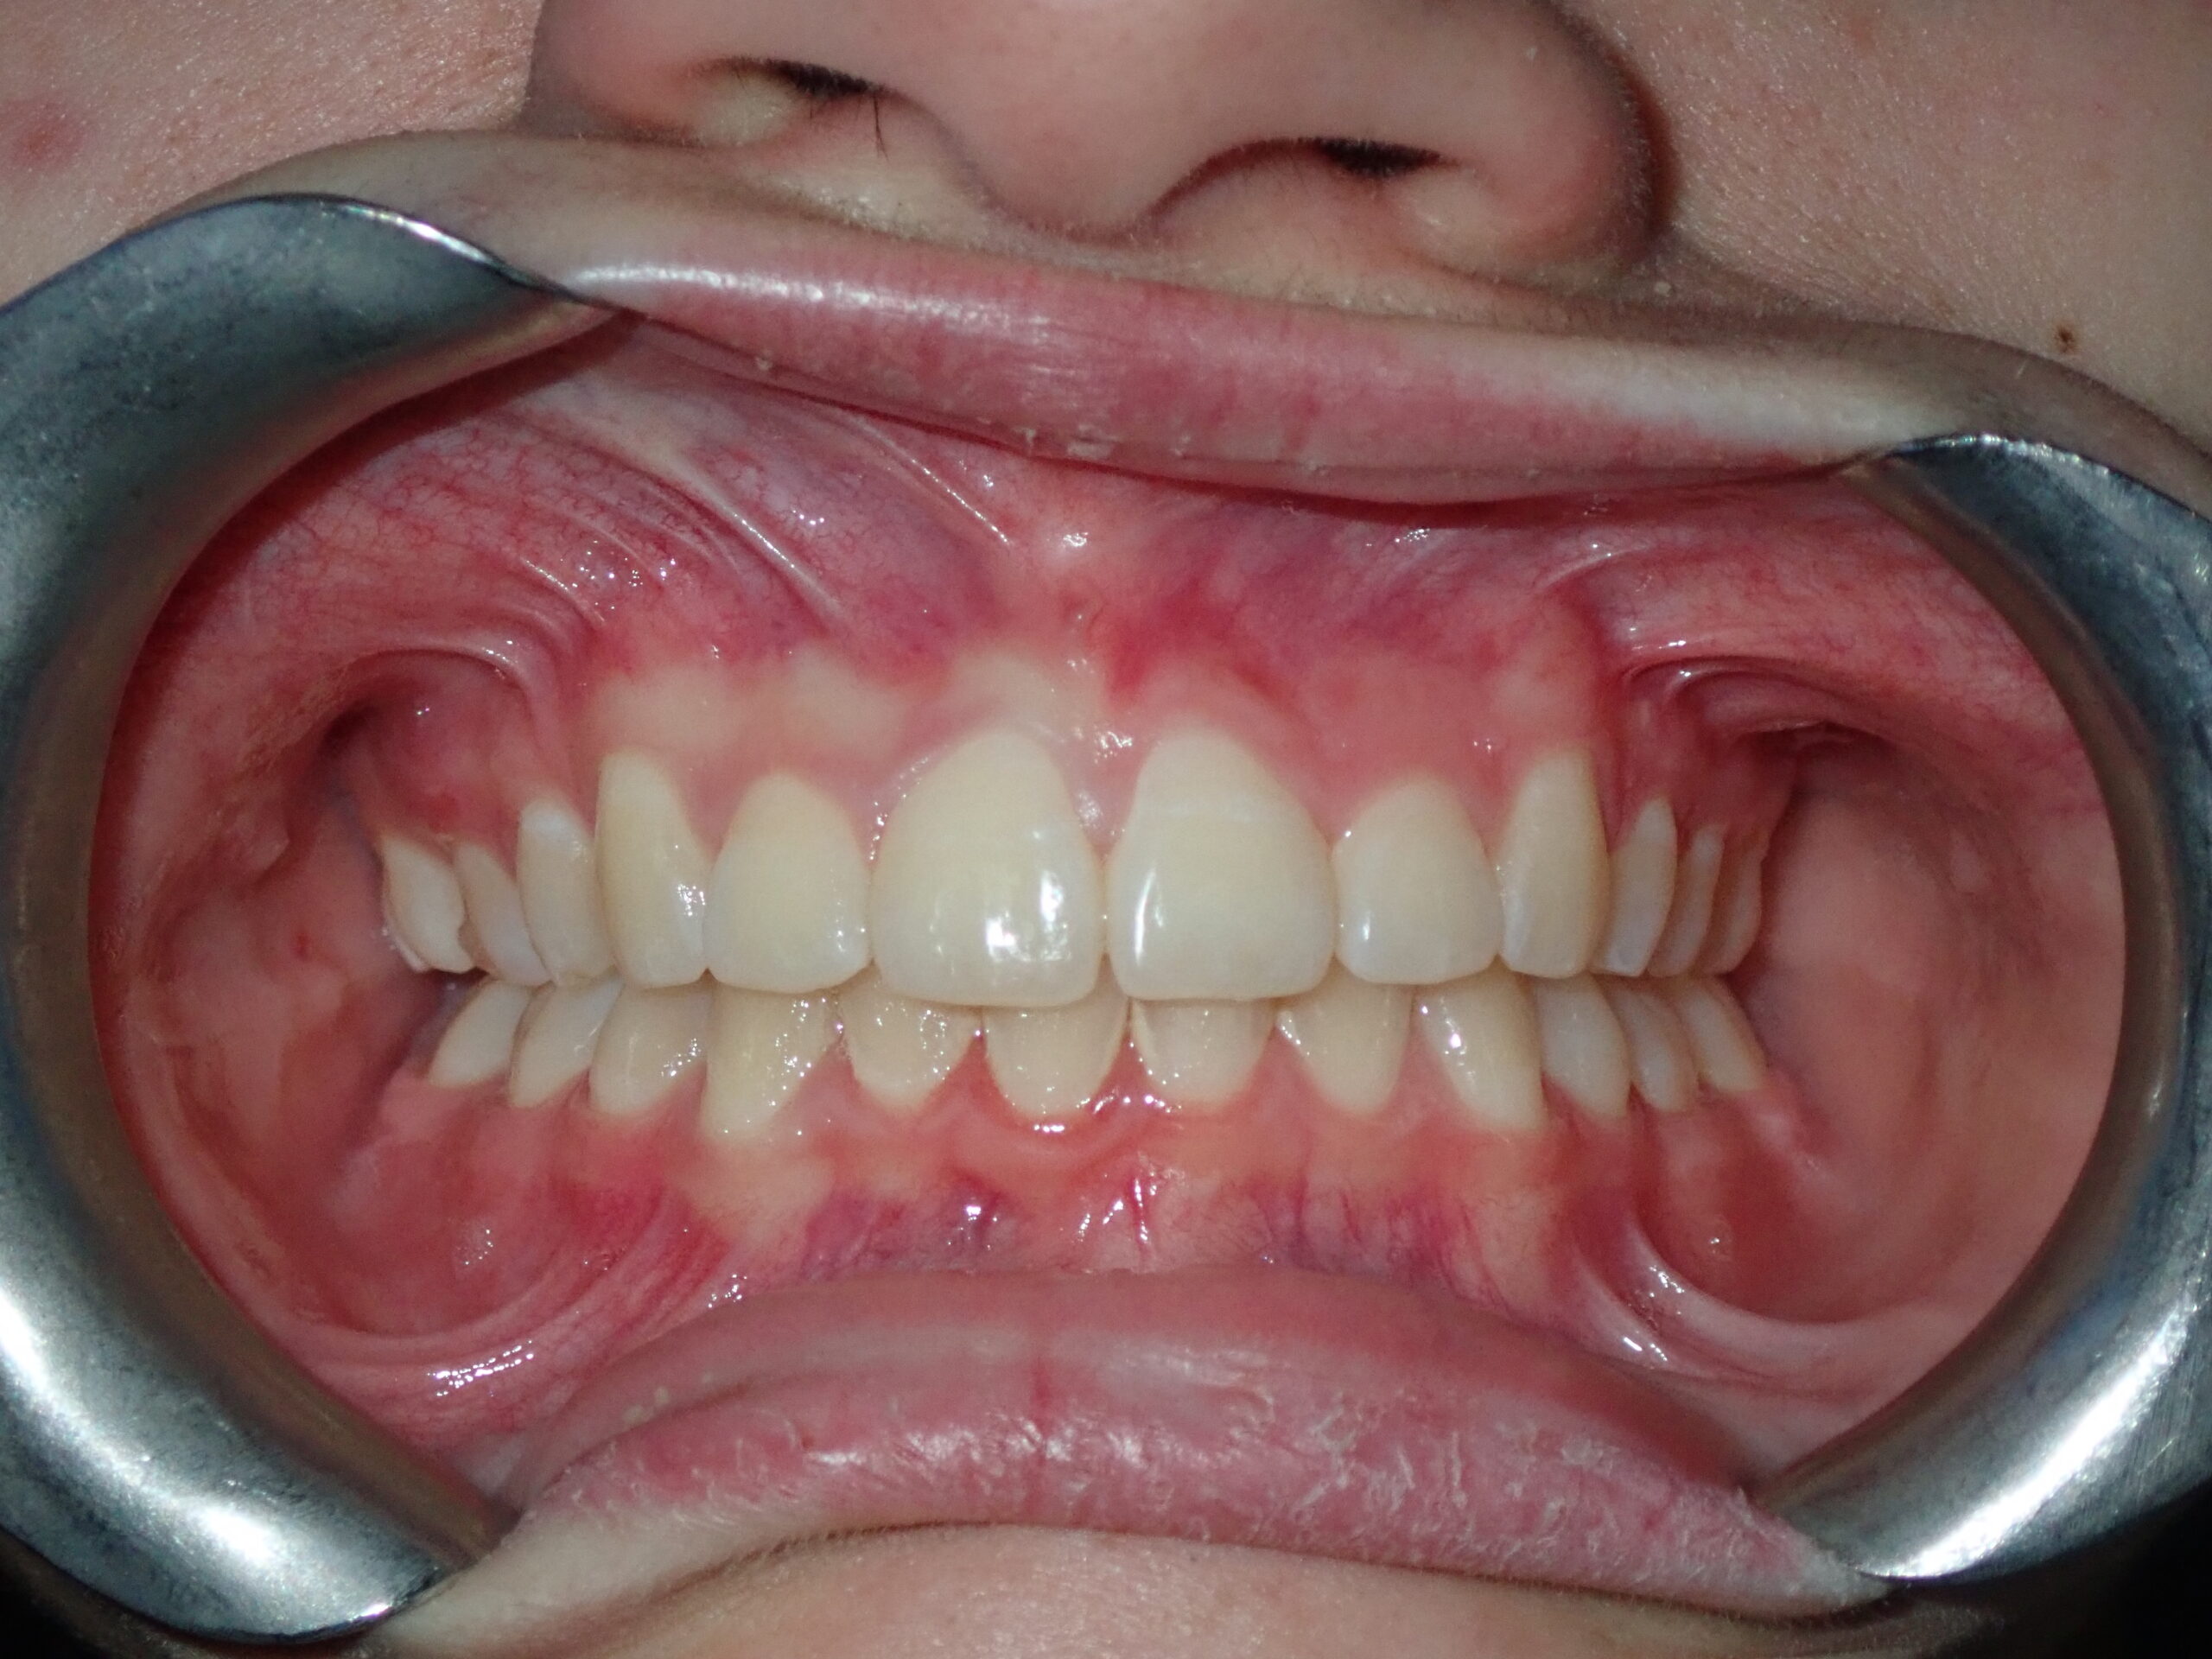

Patient Resultsنتائج المرضى

Real Results. Real Patients.نتائج حقيقية. مرضى حقيقيون.

Philosophy of Careفلسفة الرعاية

"Our mission goes far beyond merely straightening teeth. We structurally optimise the jaws and facial profile to unlock a broader smile, alleviate joint pain, and restore healthy, natural breathing — delivering life-changing results without surgery whenever possible." "مهمتنا تتجاوز بكثير مجرد تقويم الأسنان. نُحسّن بنيوياً الفكين والملامح الوجهية لإطلاق ابتسامة أوسع وتخفيف ألم المفاصل واستعادة التنفس الصحي الطبيعي — نتائج تغيّر الحياة بدون جراحة كلما أمكن."